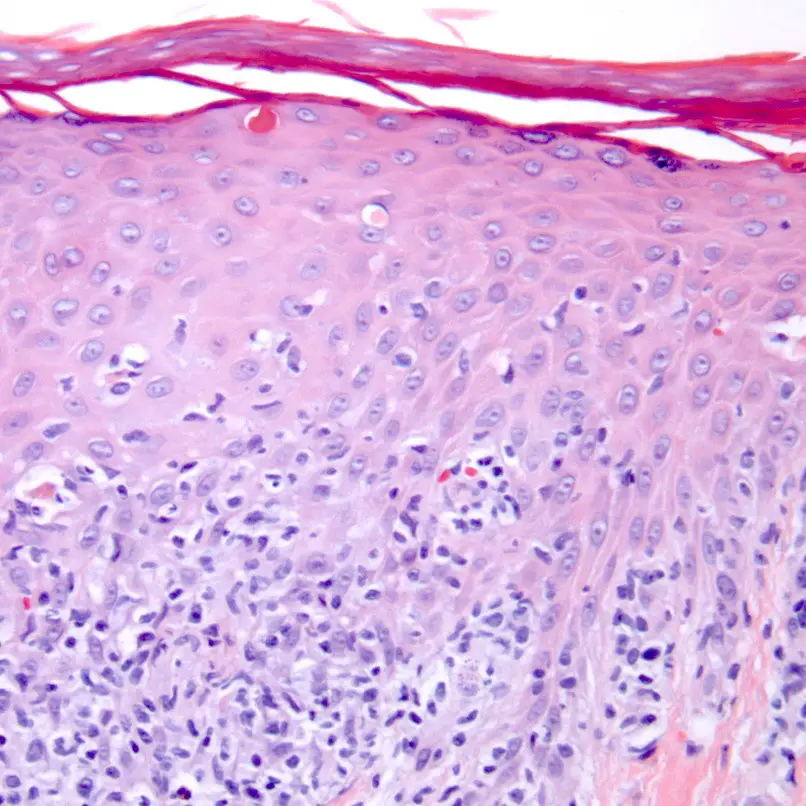

Atypical Cutaneous Manifestations in Syphilis | Actas Dermo-Sifiliográficas

Figure 3 from Manifestations of Syphilis | Semantic Scholar

Secondary Syphilis | Basicmedical Key

Infections | Plastic Surgery Key